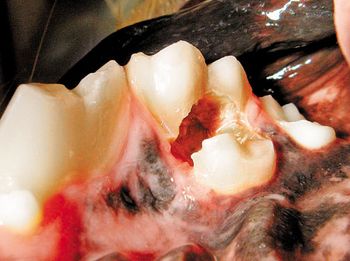

Five case studies that highlight the importance of timely veterinary dental referrals.